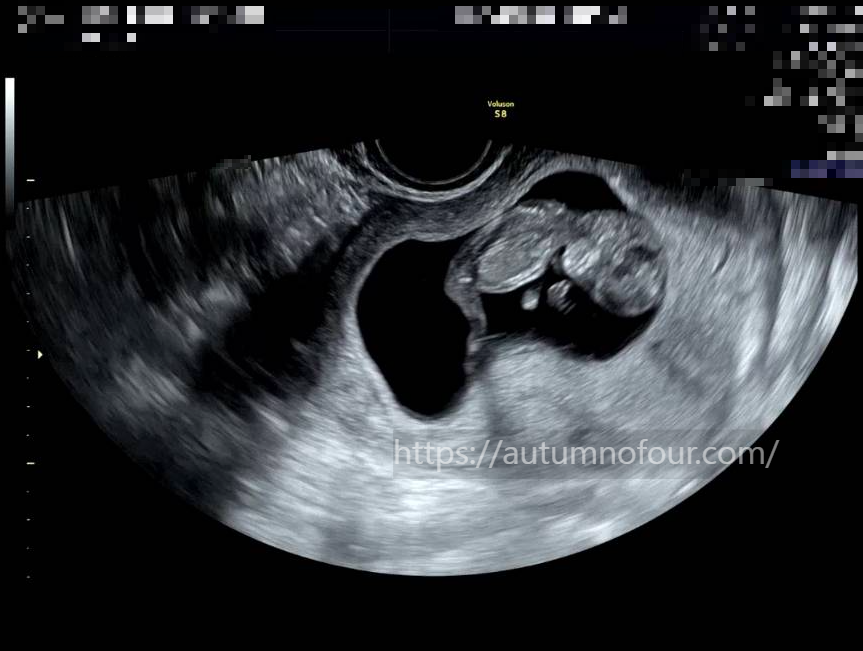

초음파를 보는데 억?? 소리가 나왔다

고새 어떻게 이렇게 많이 큰거지??????

지난번엔 팔과 다리가 정말 젤리곰 같이 찔끔(?) 나와있었는데

아주 쭈-------욱 하고 늘어나있었고,

그 덕분인지 꼬물꼬물 움직이는게 정말 잘 보였다.

손가락도 보이고, 사람형태가 된 44MM 아가 ㅋㅋㅋㅋㅋ